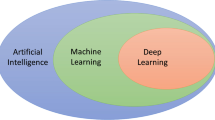

Deep learning (DL) is an advanced form of artificial intelligence that has revolutionized computer vision, leading to a rather rapid expansion into a much broader range of science and engineering disciplines, including medical imaging [1].